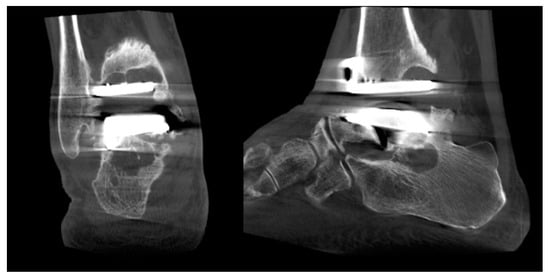

Ankle Replacement Surgery